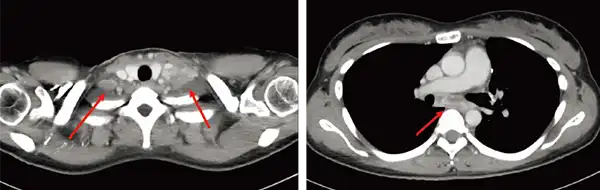

治療前造影CT

肺がんの症例です。両側鎖骨上にリンパ節があり、縦隔にもリンパ節転移があります。 従来の放射線治療では、主に脊髄の耐用線量の限界により根治的な放射線治療の投与が困難でしたが、VMATを使って、根治的な治療を行うことができました。